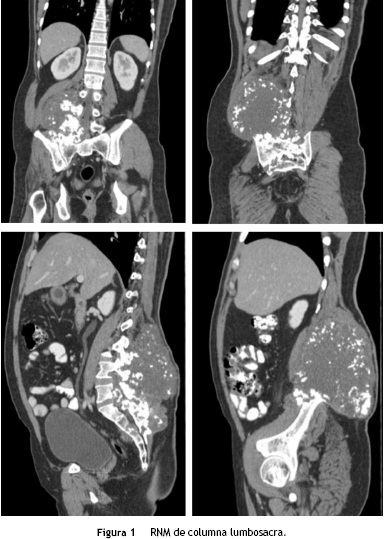

Paciente masculino de 36 años de edad, con cuadro de 2 años de evolución de masa de crecimiento lento y progresivo en región lumbosacra, asociada a lumbalgia irradiada a miembro inferior derecho, reporte de biopsia inicial con-drosarcoma bien diferenciado. El TAC evidenció una masa voluminosa de 20 cm de diámetro, localizada a nivel del músculo cuadrado lumbar derecho, con osteolisis en el arco posterior del cuerpo vertebral adyacente, del ilíaco y del sacro derechos. RMN de columna lumbosacra, mostró una neoplasia de 22 x 9 x 13 x 6 mm en la región sacrococcígea paramedial derecha, con compromiso de los músculos pre y paravertebrales e invasión de arcos vertebrales posteriores desde L2 hasta la región sacrococcígea, compromiso del foramen de conjugación derecho y extensión hacia el canal vertebral en L4-L5, desplazamiento de las estructuras de la línea media, compromiso del músculo psoas ipsilateral y aparente extensión hacia la cavidad pélvica (fig. 1). Tratamiento inicial con quimioterapia con doxorrubicina + ifosfamida (5 ciclos) extrainstitucional.